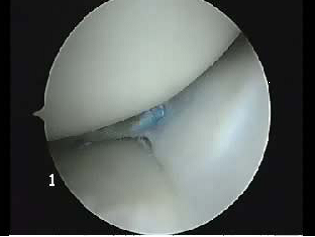

Suture méniscale (fil bleu) stabilisant la déchirure méniscale

Suites opératoires : La revalidation est plus lourde avec une absence d’appui pendant 4-6 semaines, éventuellement un appui partiel 6 semaines, afin de protéger la réparation méniscale.